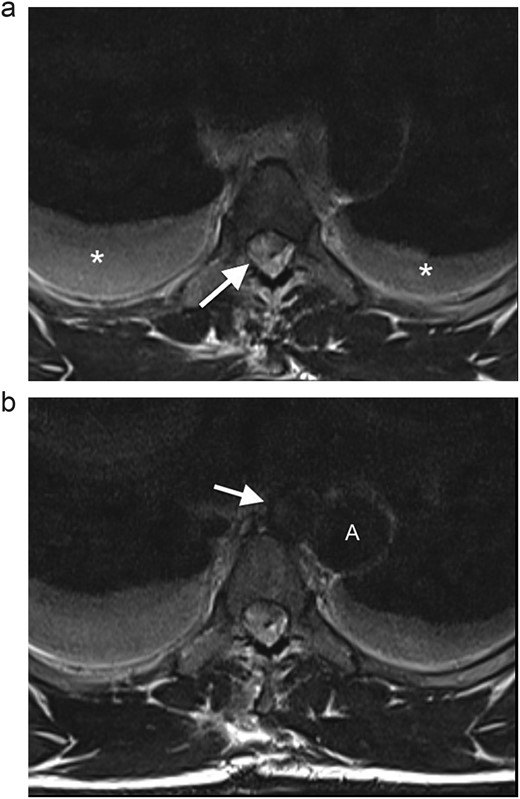

On neurological examination, the patient was suspected of having Brown–Sequard syndrome, as power and light touch sensation was reduced in the right lower limb, with reduced sensation over the right lower abdomen. Furthermore, there was decreased pain sensation in the left lower limb. He had normal bladder function and normal sensation over the sacral area. The patient was reviewed by the Neurosurgical team and referred for an magnetic resonance imaging (MRI) of the spine. The MRI demonstrated a penetrating injury to the mid-thoracic spine with a right hemicord transection at the level of T5 (Fig. 1a). There was an associated right spinal epidural hematoma with resultant compression of the cord and cord oedema (Figs 1b and 2a). The Neurosurgery team elected to manage the injury conservatively.

(a) Axial T2WI MR at the midthoracic level demonstrates an epidural hematoma in the right lateral spinal canal with compression of the cord (arrow) and bilateral hydrothoraces (*). (b) Axial T2WI MR shows a round lesion (arrow) inseparable from the medial aspect of the mid-thoracic aorta (A), with an isointense signal to the thoracic aorta.